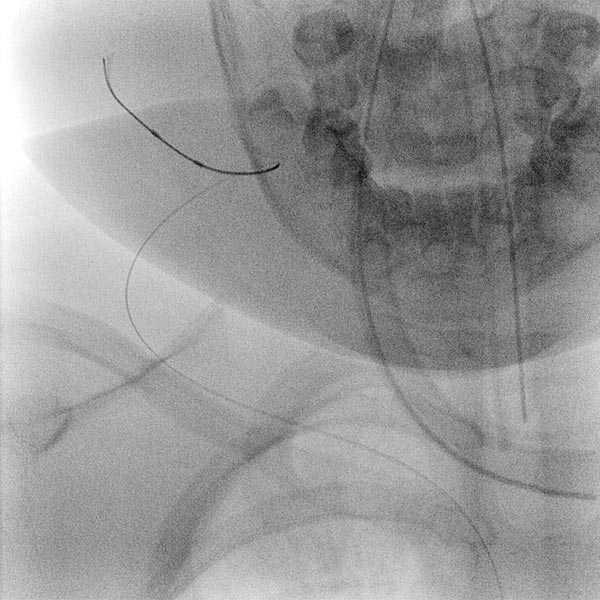

In view of the lack of regression, probably also caused by the relevant stenosis of the venous outflow, the decision to embolize the hemangioma was made in the 24th month of life in order to induce regression of the mass. In a first step during intervention, the venous outflow (right external jugular vein) was cannulated retrogradely from transvenously.

A small balloon catheter was then inserted to block the venous outflow prior to embolization to prevent unintended dislocation of the arterially injected embolic agent to the venous side.